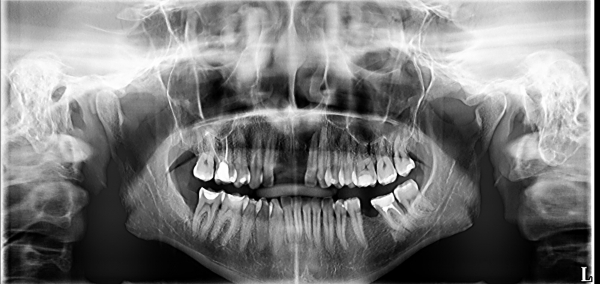

Готовлюсь к имплантации. Сделали снимки: киста на 22, 23 зубах. Назначили лечение, затем через два месяца цистэктомия. Очень опасаюсь, что до этого момента случиться обострение, вплоть до удаления зуба.

И каковы шансы на успешную имплантацию по снимку? Лечение назначено через неделю.

По этому снимку невозможно планировать операцию и диагностировать Вашу проблему. Успех операции на 36 зубе зависит от профессионализма хирурга, условия хорошие. Что касается передних зубов — к сожалению, по этому снимку ничего не видно. Приезжайте ко мне, я Вас посмотрю.